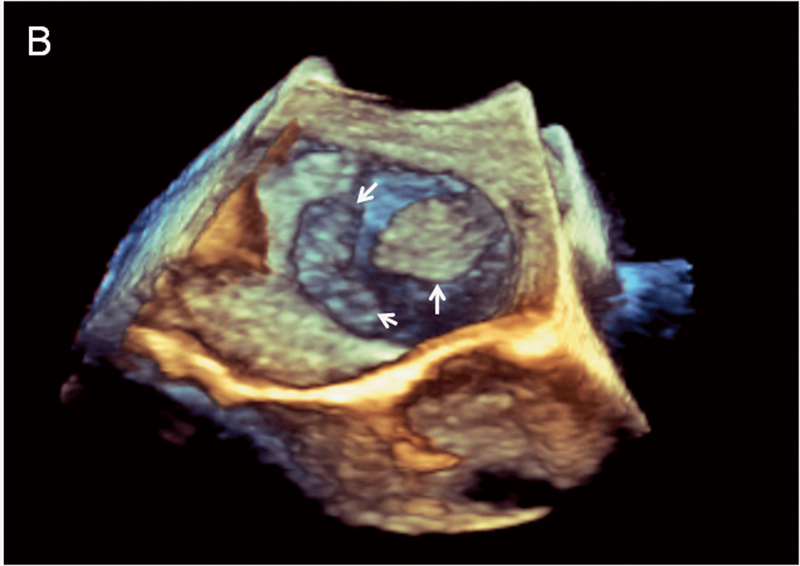

فحوصات تشخيصية لبعض امراض القلب والشرايين التاجية